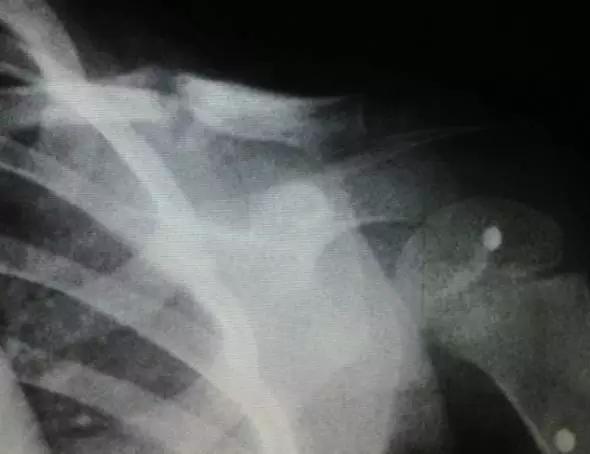

图2:锁骨骨折愈合过程中的骨痂形成